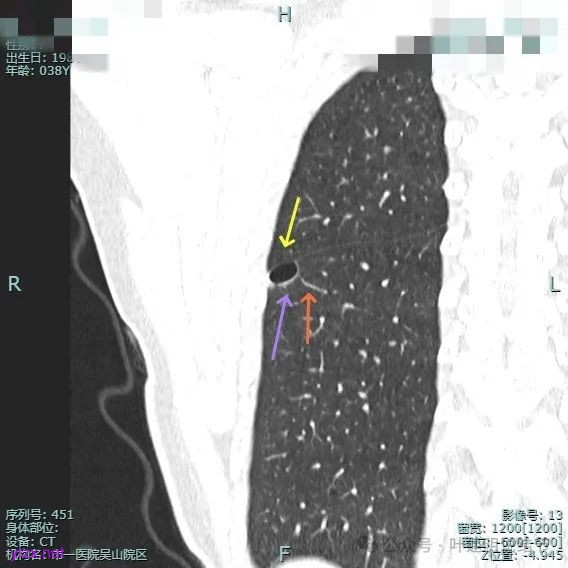

非薄层平扫上这个层面比较明显,似一囊腔,壁厚薄欠均匀。

薄层上看病灶贴着叶间裂与胸膜,此层囊壁薄,囊腔明显。

囊壁局部有增厚。

囊壁局部较厚,但囊壁内也是有小空泡的,病灶贴着胸膜。